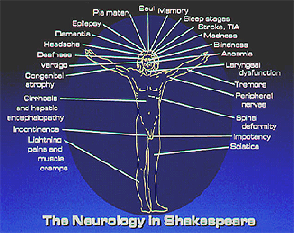

Many volumes and articles describing his medical knowledge have been written over the past two centuries. As a clinical neurologist the symptoms, signs, and diseases of the nervous system that appeared in the various characters in the plays, and in his poetry, are depicted in the Vitruvian figure below. Some depictions are forthright such as stroke, epilepsy, headache, vision and hearing abnormalities, vertigo, dementia, delirium, psychosis, sciatica, birth injuries of nerves, incontinence and impotency.

What are not so overt to the lay person for example, are very subtle, but highly accurate, descriptions of protein’s deleterious effect on an alcoholic with cirrhosis of the liver, and several of the complications of late stage syphilis. How they appear in his works are most fascinating, and I discuss them in my personal presentations to audiences and in my publications.